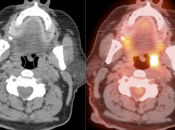

Unilateral FDG-Avid Tonsil (or Relative Increased Avidity of One Tonsil):

Special care is required when assessing the incidental finding of a unilateral hot tonsil (or relative increased uptake within one tonsil) — even though most unilateral hot tonsils are benign. Proposed techniques for assessment have included SUV threshold cutoff values, metabolic tumor volume assessment, and SUV ratios.

Unfortunately, it is advisable to raise at least a degree of concern for most FDG-avid unilateral tonsillar findings. The level of suspicion, of course, depends on the presentation.

At PETCTMD, we utilize the following practical approach for the incidental finding of a unilaterally FDG-avid tonsil:

- NON-ENLARGED AND:

- Unilaterally Avid (≥ Liver Uptake)

- OR

- Uptake “Unquestionably” > Contralateral Tonsil

We typically report, “While this uptake is typically physiologic or inflammatory in nature, direct visualization may be of diagnostic value, if clinically warranted.”

(If the uptake is < liver uptake, we presume the metabolic activity to be physiologic or inflammatory)

- UNILATERALLY ENLARGED AND:

We typically report, “While its increased size and increased metabolic activity may be inflammatory in nature, direct visualization may be warranted to exclude a neoplastic process in this case.”